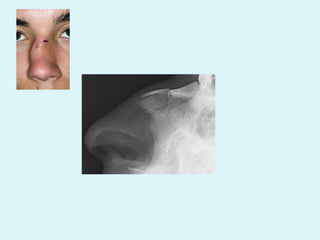

Fractures of Nasal bone and Septum

 Diagnosis

 PHYSICAL examination

 Xray – lateral views and Water’s view

 CT PNS with 3D reconstruction of facial bones